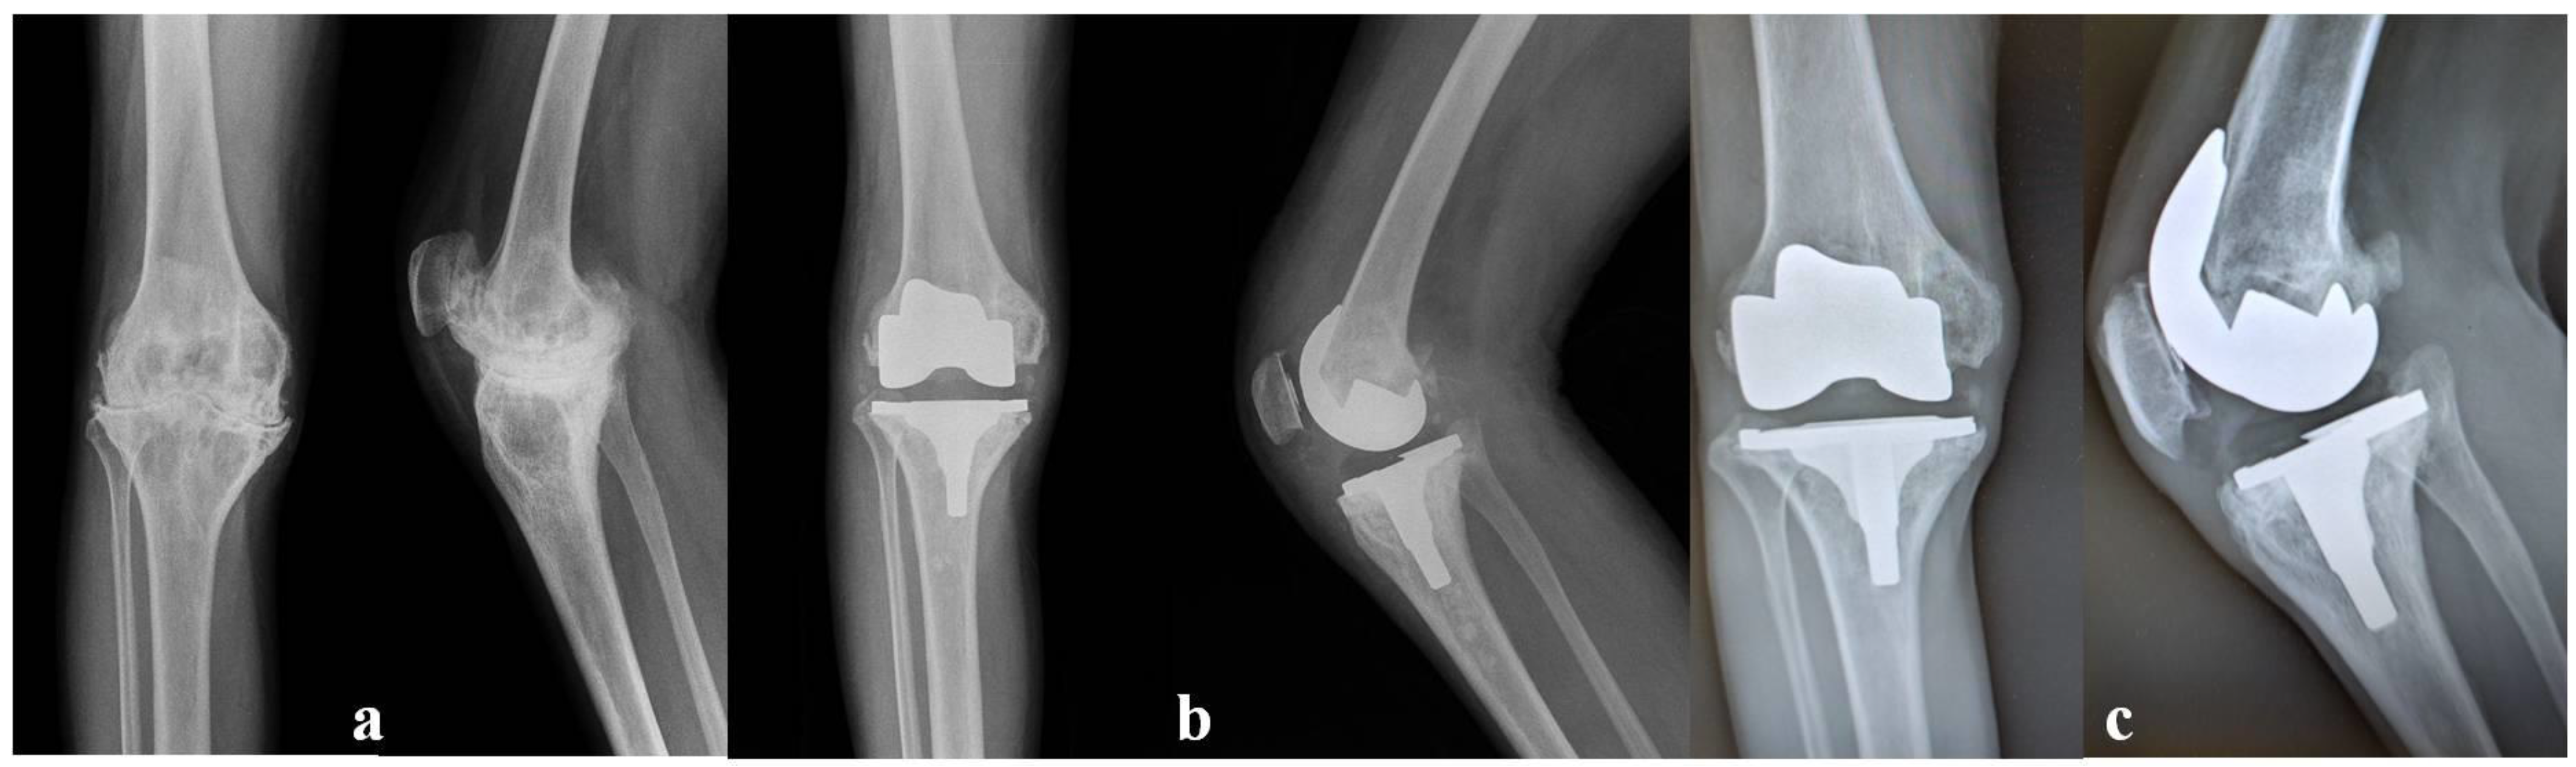

- Innocenti, M.; Matassi, F.; Carulli, C.; Nistri, L.; Civinini, R. Oxidized zirconium femoral component for TKA: A follow-up note of a previous report at a minimum of 10 years. Knee 2014, 21, 858–861. [Google Scholar] [CrossRef]

- Civinini, R.; Matassi, F.; Carulli, C.; Sirleo, L.; Lepri, A.C.; Innocenti, M. Clinical Results of Oxidized Zirconium Femoral Component in TKA. A Review of Long-Term Survival. HSS J. 2017, 13, 32–34. [Google Scholar] [CrossRef]

- Innocenti, M.; Civinini, R.; Carulli, C.; Villano, M.; Linari, S.; Morfini, M. A modular total knee arthroplasty in haemophilic arthropathy. Knee 2007, 14, 264–268. [Google Scholar] [CrossRef]